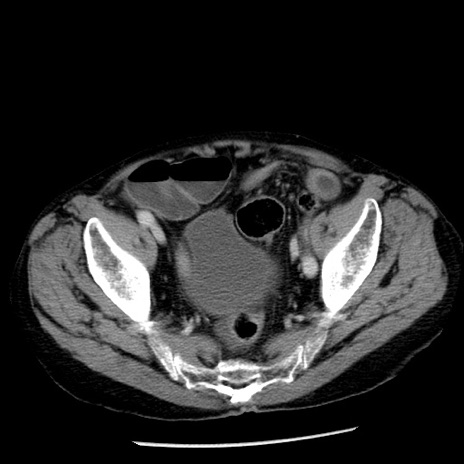

症例26(横断像)

【症例】80歳代男性

【主訴】嘔吐

【現病歴】昨晩2回嘔吐あり、今朝になっても嘔吐あり。来院。

【既往歴】胃潰瘍

【身体所見】意識清明、BT 37.6℃、BP 166/95mmHg、HR 100bpm、SpO2 97%、腹部:平坦・軟、腸蠕動音聴取良好、圧痛なし。

【データ】WBC 21900、CRP 1.46